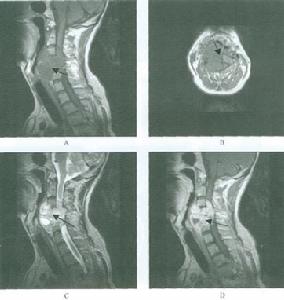

CT檢查可清楚地顯示骨折及移位的情況,尤其在患者強迫體位造成普通X線片上解剖結構顯示不清時,Blacksin和lee報告100例嚴重創傷患者常規拍攝頸椎側位片並以常規頸枕部CT替代開口位片結果CT發現7例8處骨折,3處在枕骨大孔,5處位於C12水平,而普通X線頸椎位片除2例顯示了椎前軟組織陰影增寬外,未發現骨折征,顯示CT檢查的重要性和優越性。MRI檢查可清楚地顯示骨折移位造成脊髓受壓的情況及脊髓損傷的程度,還有鄰近軟組織損傷的情況Pederson報導1例齒狀突骨折傷後16周,因持續頸部疼痛和進行性神經壓迫症狀而行MRI檢查始獲診斷MRI顯示寰樞椎複合體完全骨折伴後脫位,脊髓受壓嚴重。此時複習X線片發現受傷當天所攝頸椎側位片顯示齒狀突骨折,骨折線通過狹部(為ⅡC型骨折),骨折端向後移位約20mm,再行CT檢查確定了20mm的齒狀突骨折後移位,顯示傷後16周骨折移位未發生變化。